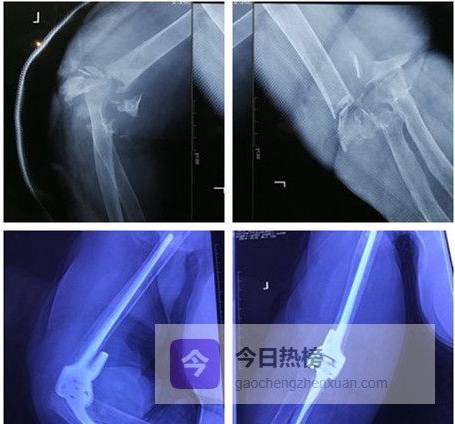

02复杂肘关节骨折:到底“复杂”在哪?

单纯脱位只是“软组损伤”,复位后多数能安稳度日;一旦合并桡骨头、冠状突或尺骨鹰嘴骨折,就升级为“复杂肘关节脱位”。这些“关键零件”碎成几块,就像拼图少了关键几片,后期出现慢性不稳、关节退变的风险陡增。

04置换策略:把“旧零件”换成“新关节”

当骨折粉碎到“无法拼回”、关节面软骨大面积缺失,或患者年龄偏大、活动量有限时,肘关节置换(TEA)成为快速恢复功能的捷径。金属肱骨头+聚乙烯衬垫替换掉磨损的远端肱骨与尺骨,术后第二天即可开始康复。